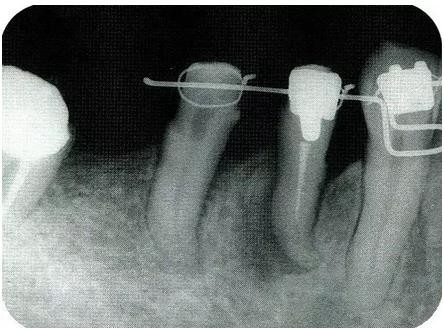

圖18-7(左),8(右)  佩戴最終修復(fù)體的口腔內(nèi)照片和X線片,牙槽骨平坦化,牙周袋探診2mm以內(nèi)。